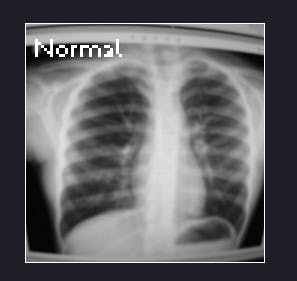

Finally, move the board to any X-Ray or download our dataset images from here and that’s it you’re done!